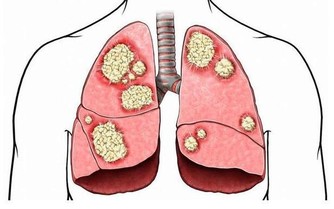

首先,喝酒不養生。酒精是1類致癌物,多喝一口酒,對身體的傷害就多一分。